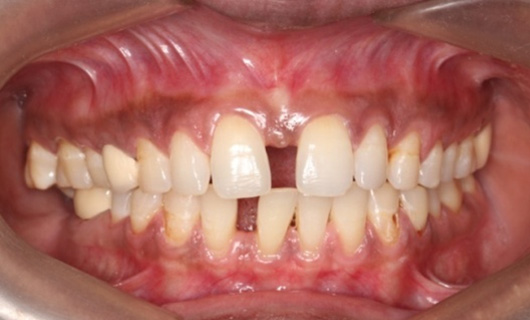

Like braces, Invisalign Braces straighten teeth by placing trays of special material over the teeth in their natural position. A gentle and constant force is used to move the teeth into the desired position without having to go through the hassle of metal wires and brackets. Through digital scanning, they are customized for every patient. Over time, they become a part of the body, since they are so snugly fitting. You are free to eat and drink anything since you will be removing all foods before every meal.